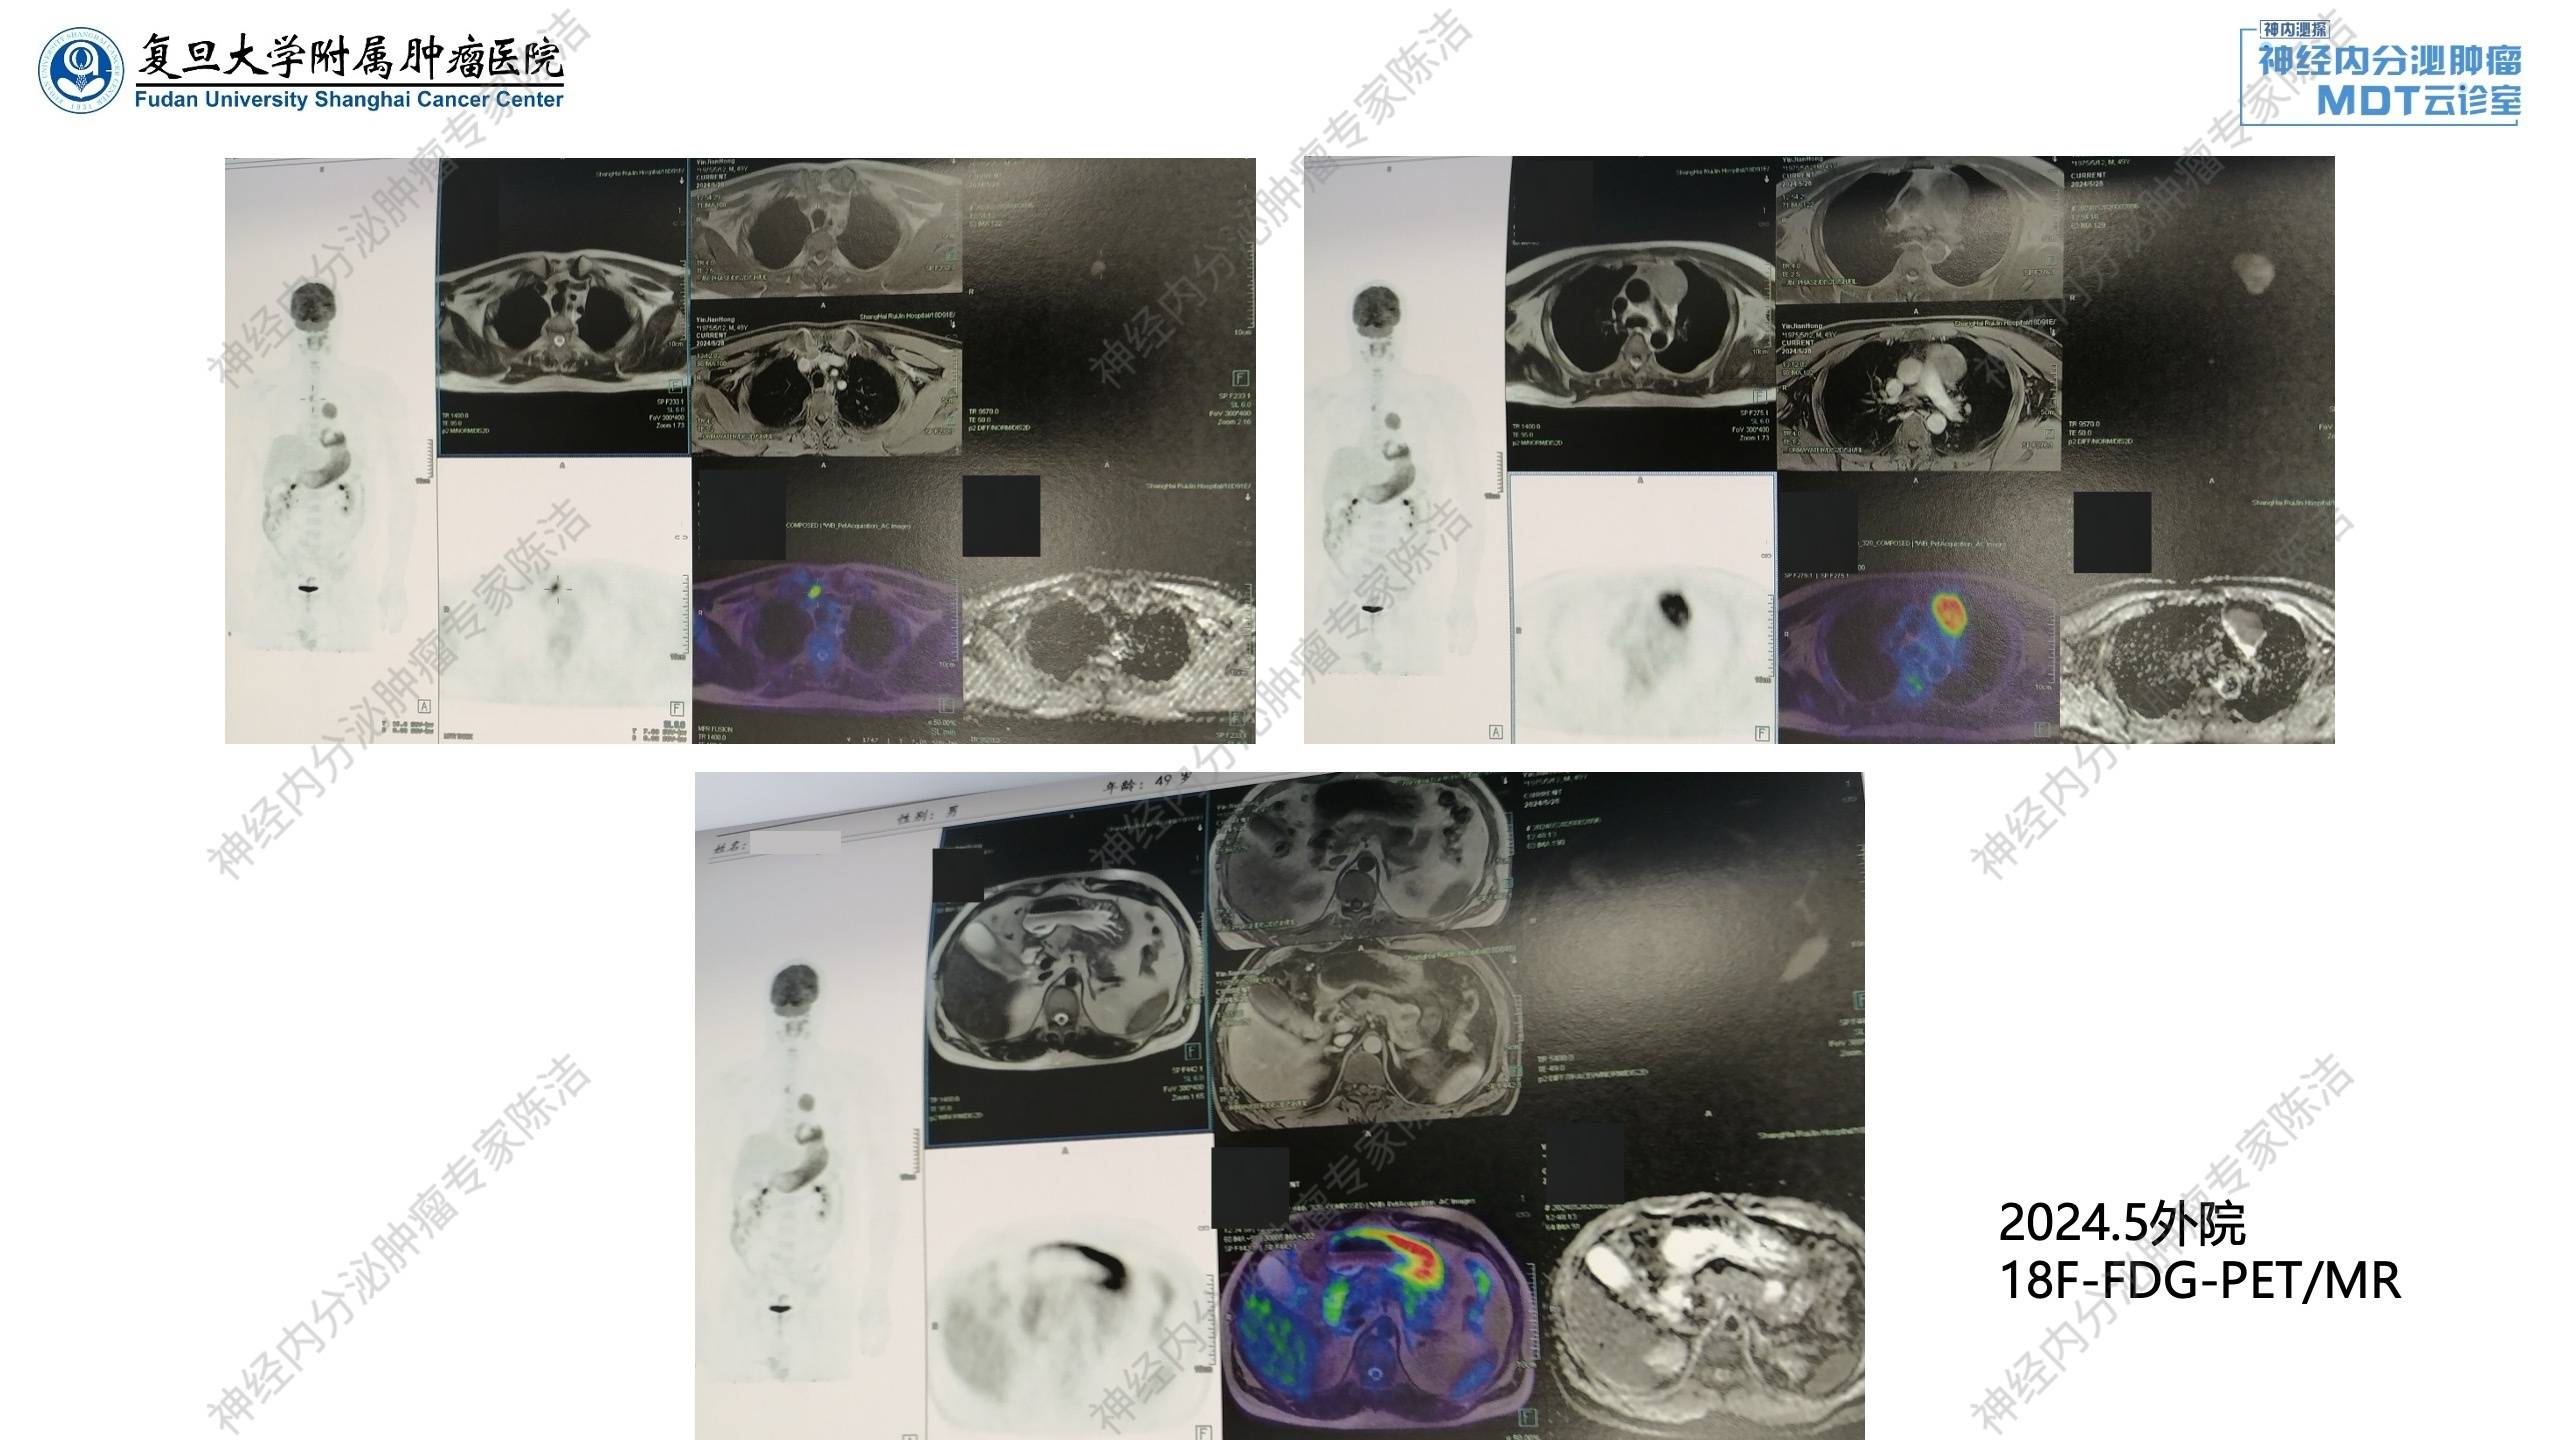

2024年5月:外院腹部增强CT发现胰腺多发囊实性占位,MEN-1可能。18F-FDG-PET/CT提示胰腺多发囊实性占位,增强后病灶边缘强化,代谢未见明显增高,考虑神经内分泌肿瘤可能;前纵隔异常信号灶,增强可见边缘轻度强化,代谢增高,恶性病变待排,胸腺来源?胸骨上窝肿大淋巴结,代谢增高,转移性病变不除外;胃粘膜皱襞宽大伴弥漫性代谢增高。

68Ga-DOTATATE-PET/MR提示胰腺多发囊实性占位,DOTATATE摄取增高,首先考虑多发胰腺神经内分泌瘤;前纵隔异常信号灶,DOTATATE摄取增高,结合FDG-PET考虑胸腺来源恶性病变可能,类癌?胸骨上窝异常信号灶,DOTATATE摄取增高,转移性淋巴结可能;左侧甲状腺上极背侧及左侧甲状腺下极点状DOTATATE摄取增高灶。

核医学科徐俊彦教授:外院FDG-PET提示前纵隔病灶显示清晰,糖代谢很高,且有区域淋巴结转移,但胰腺部位FDG低代谢。与之相反,DOTATATE-PET提示前纵膈病灶生长抑素仅轻度摄取,而胰腺可见多发生长抑素受体高表达病灶。考虑胰腺病灶及纵隔病灶为双原发神经内分泌肿瘤,结合病史,符合多发性内分泌腺瘤病1型表现。

放射诊断科汤伟教授:腹部增强CT显示胰体部有一个比较大的富血供占位,中央伴有一些囊变。除此之外,胰头、胰体、胰尾还有多个富血供占位。这跟第一个病例比较相似,为多灶性胰腺神经内分泌瘤的改变。